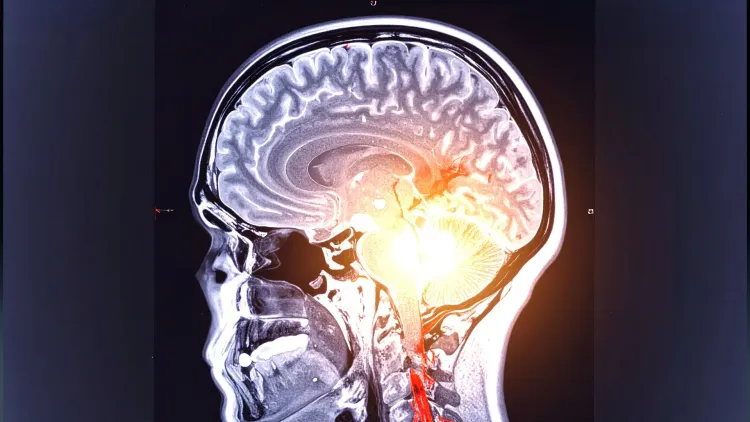

New Delhi, June 10 (NationPress) Recent research indicates that bacteria residing in the oral cavity and gastrointestinal tract might significantly influence the advancement of cognitive decline associated with Parkinson's disease. The study highlights specific alterations in the gut microbiome linked to the transition from mild memory issues to dementia, a prevalent and troubling symptom of the condition.

Diagnosing Parkinson's in its early phases remains challenging; however, these microbiome changes could serve as potential early indicators of the disease, according to researchers from King's College London.